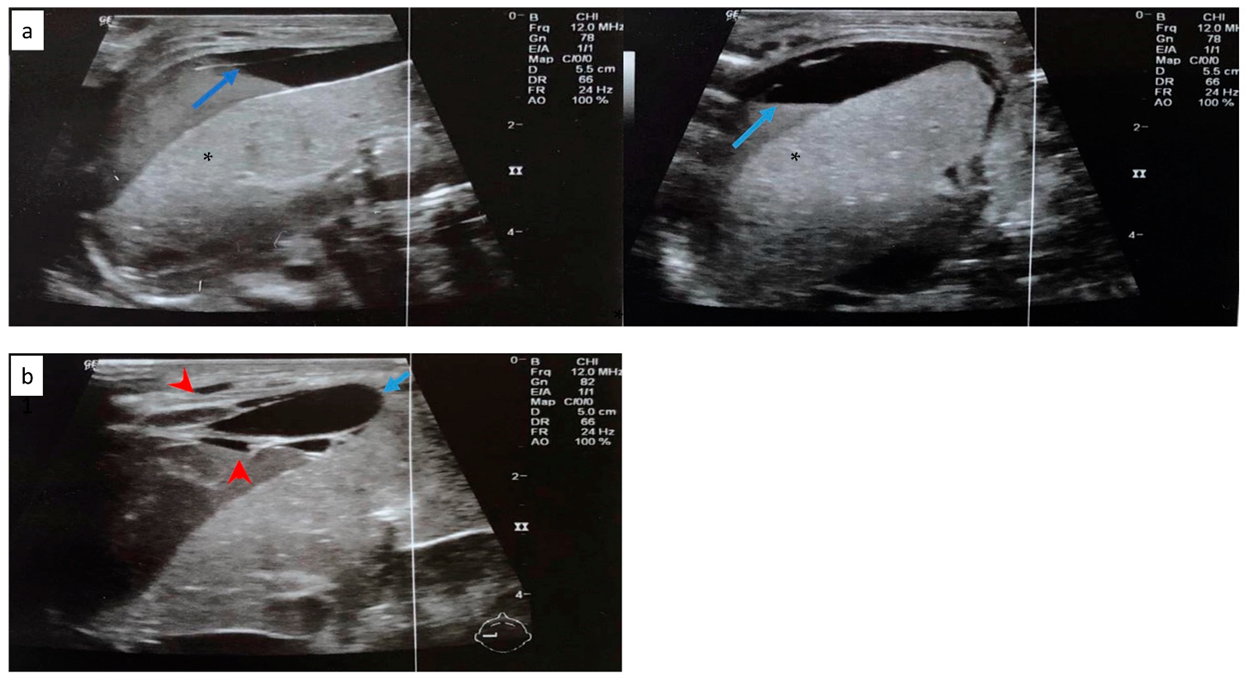

Cranial ultrasound revealed a 1st-degree IVH. Abdominal ultrasound revealed free perihepatic, perisplenic, and inter-intestinal fluid collection (Figure 5a). Abdominal distension was noted in the radiography (Figure 6).

Figure 5.

(a) Free perihepatic fluid collection (blue arrow) in abdominal ultrasound. (b) Abdominal ultrasound depicting subcapsular hematoma of the liver (blue arrow) and hemorrhagic collections in the peritoneal cavity (red arrowhead). Normal liver parenchyma is noted with asterisk (*).

The following day, the clinical condition of the neonate deteriorated, with persistent hypotension, edema and without urine output. A second abdominal ultrasonography revealed subcapsular hematoma of the liver and the spleen and hemorrhagic collections in the peritoneal cavity (Figure 5b). The blood cultures and peritoneal fluid cultures grew Klebsiella pneumoniae. Despite the supportive treatment, the neonate worsened dramatically and deceased on the 8th day.